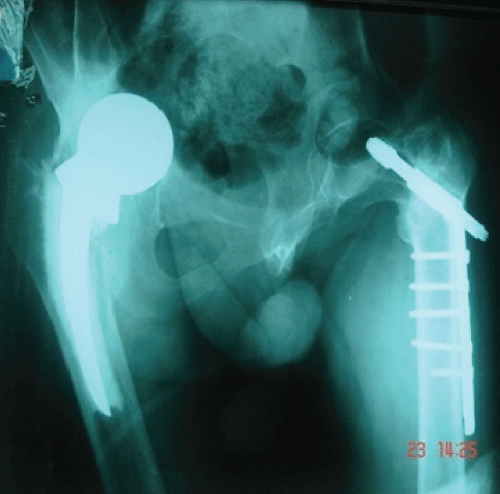

Patient number 5 presented late with several complications following the primary treatment. Dynamic hip screw for left NoF and hemiarthroplasty for right NoF were done on primary treatment (Figure 5), but he showed inferior results after surgery. His family refused any further surgical intervention due to the bad history.

Figure 5: Plain X-ray demonstrates failure of dynamic hip screw for left NoF and hemi-arthroplasty for right side.